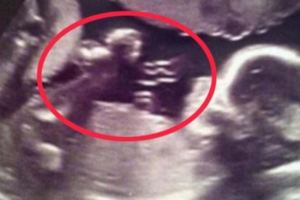

媽媽照超音波照到一半,醫生發現她肚子有「這些東西」!